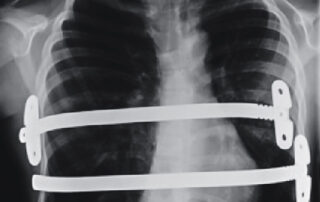

During the Nuss procedure, Dr Schewitz will make two small incisions in the side of the chest. A stainless steel bar is then inserted behind the deformed breastbone and attached the outer edge of the ribs. The bar will then be turned to raise the breastbone. This bar is left in place to raise the breastbone and correct the deformity over 3 years. The bar is then removed.